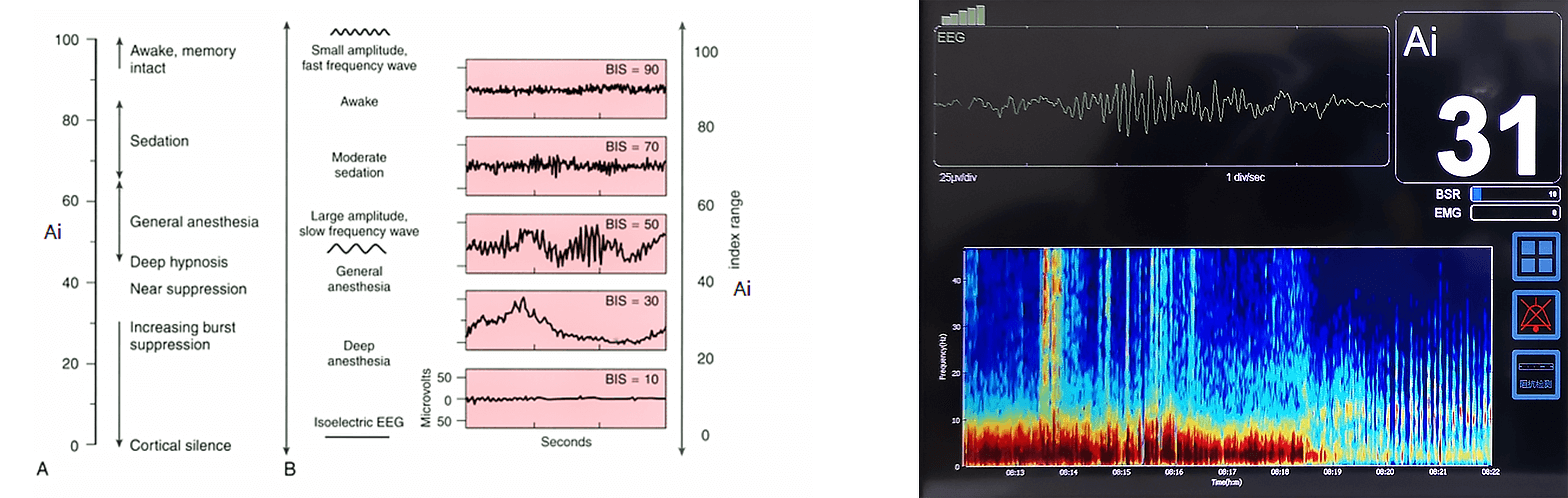

L'indice di profondità dell'anestesia ai sfrutta l'analisi del segnale eeg per quantificare accuratamente la profondità dell'anestesia. Mentre i pazienti passano dalla sveglia all'anestesia profonda, i segnali eeg presentano modelli distinti, compresi un aumento dell'attività dell’onda δ, la soppressione dello scoppio e eventuali stati isoelettrici.

Principi di baseAI calcola un indice numerico analizzando le caratteristiche eeg su più dimensioni: dominio della frequenza, analisi bispettrale, dinamica nel dominio del tempo e complessità del segnale. Modelli statistici multivariati mappano questi cambiamenti in un indice continuo, fornendo una valutazione affidabile e in tempo reale della profondità dell'anestetico.

Un indice multivariato derivato dalla frequenza del segnale eeg, dal dominio del tempo e dalle metriche di complessità per quantificare la coscienza dal sveglio (100) alla soppressione completa (0). Soglie chiave: 100 = sveglio, 70 = sedazione leggera, 60 = anestesia generale, 40 = ipnosi profonda, 0 = eeg isoelettrico (nessuna attività cerebrale).

Ai (indice di consapevolezza dell'anestesia)Un indice multivariato derivato dalla frequenza del segnale eeg, dal dominio del tempo e dalle metriche di complessità per quantificare la coscienza dal sveglio (100) alla soppressione completa (0). Soglie chiave: 100 = sveglio, 70 = sedazione leggera, 60 = anestesia generale, 40 = ipnosi profonda, 0 = eeg isoelettrico (nessuna attività cerebrale).

BSR (rapporto di soppressione del burst)Quantifica la percentuale di tempo eeg mostra soppressione(bassa ampiezza o linea piatta) intercalato con scoppi- indicativo di anestesia profonda.